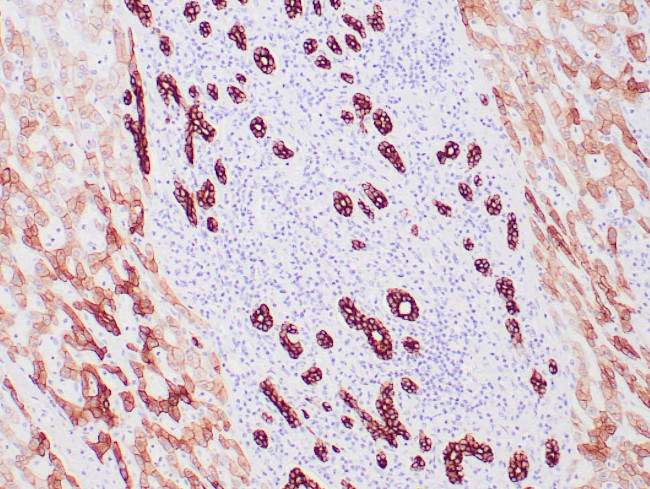

A recommended positive control tissue for this product is Epithelial cell (Tonsil, Prostate, Pancreas, colon, Thyroid, etc.), however positive controls are not limited to this tissue type.

The primary antibody is intended for laboratory professional use in the detection of the corresponding protein in formalin-fixed, paraffin-embedded tissue stained in manual qualitative immunohistochemistry (IHC) testing. This antibody is intended to be used after the primary diagnosis of tumor has been made by conventional histopathology using non-immunological histochemical stains.

Keratin 8 belongs to the type B (basic) subfamily of high molecular weight keratins and exists in combination with keratin 18. Keratin 8 is primarily found in the non-squamous epithelia and is present in majority of adenocarcinomas and ductal carcinomas. It is absent in squamous cell carcinomas. Hepatocellular carcinomas are defined by the use of antibodies that recognize only cytokeratin polypeptides 8 and 18.

Antibody is used with formalin-fixed and paraffin-embedded sections. Pretreatment of deparaffinized tissue with heat-induced epitope retrieval or enzymatic retrieval is recommended. In general, immunohistochemical (IHC) staining techniques allow for the visualization of antigens via the sequential application of a specific antibody to the antigen (primary antibody), a secondary antibody to the primary antibody (link antibody), an enzyme complex and a chromogenic substrate with interposed washing steps. The enzymatic activation of the chromogen results in a visible reaction product at the antigen site. Results are interpreted using a light microscope and aid in the differential diagnosis of pathophysiological processes, which may or may not be associated with a particular antigen.